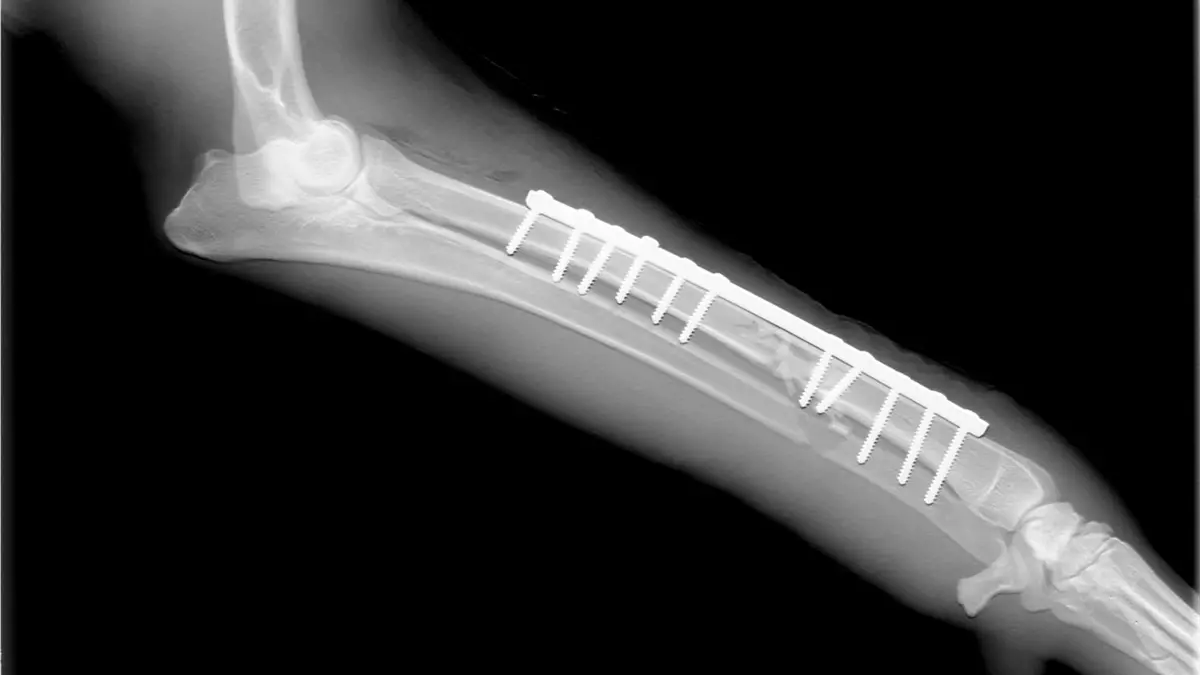

Los especialistas examinaron una serie de implantes, como tornillos utilizados en intervenciones quirúrgicas, e identificaron bacterias y hongos en ellos, a pesar de que los pacientes no han mostrado signos de infección.

Los aditamentos estudiados van desde tornillos y rodillas, hasta marcapasos y se trabajó con pacientes de cinco hospitales de la capital de Dinamarca, en diferentes grupos: con aflojamiento aséptico (cirugías de cadera), implantes craneofaciales, fracturas curadas y recién enfermos con implantes.

De las prótesis examinadas, la mayoría de los tornillos habían sido colonizados por bacterias, y en todos los casos ninguna de las bacterias u hongos eran patógenos como el estafilococo.